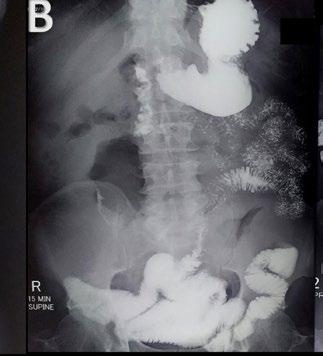

BACKGROUND AND AIMS

The aim of the study was to establish a quali-quantitative fluoroscopic severity assessment for achalasia, comparable to the equivalent clinical Eckhard scoring system (ESS).

MATERIALS AND METHODS

From September 2020–August 2022, 69 patients already diagnosed with achalasia, and scored with ESS, were recruited and evaluated with the authors’ fluoroscopy barium protocol. The anteroposterior (AP) sequence was used to divide the oesophagus into nine segments, according to Brombart's classic description, plus the gastro-oesophageal junction. Three scoring items were chosen, after a profiling study of achalasia, to depict the features, some mutually exclusive, of the three clinical subtypes: lumen dilation, stasis, and spasm. Each oesophageal segment was scored for the three items (1 point given if the item was present; 0 points given if no item). The In Vivo Assessment of Achalasia (IVA) score was calculated by summing points up, until a maximum of 20 points for each subtype was reached. IVA scores were then normalised on a 0–12 scale to be compared to ESS.

RESULTS

IVA and ESS scores were not found to be statistically diverging in 60/69 patients (86.95%; p=0.05). IVA scores were diverging, and superior to ESS in 6/69 patients (8.69%); in this group of patients, the ESS 'chest pain' and 'weight loss' items were found to be biasing factors. IVA scores were inferior to ESS in just 3/69 patients (4.34%). In all patients with a diverging IVA score (9/9), ESS scores were found to be lower than 6/12.

CONCLUSION

IVA score was found to be consistent and compatible with ESS scores, especially in patients with moderate-to-severe achalasia.

The apparent superiority of imaging scores in a small proportion of patients might instead be used as a revealing tool to call out patients in which the ESS does not reflect the disease's severity, due to internal biases. ●